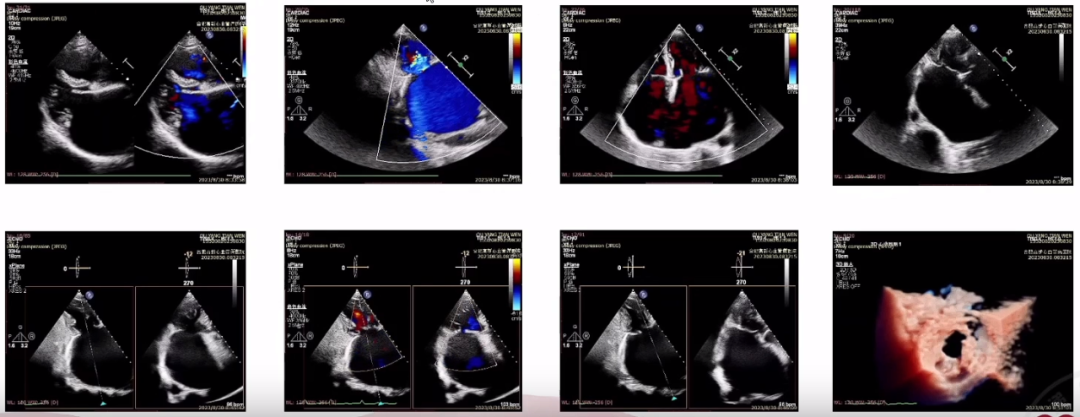

术前经胸超声心动图示,左右心房内径增大,二尖瓣关闭不全(重度,CarpentierⅠ,4+)。2区二尖瓣前叶长度约29mm,后叶长度约19mm,二尖瓣前、后叶增厚,后叶卷曲,活动略受损,二尖瓣瓣尖对合错位,错位高度约8mm,瓣尖距离瓣环深度约12mm,致使瓣叶闭合不拢,二尖瓣口面积约4.6㎝²,收缩期探及大量反流,主要来源于2区和3区,反流缩流颈宽约8mm,最大反流面积27.6㎝²,反流分数约28%,Pisa法测量反流有效面积0.47㎝²,反流容积约77ml。

(术前超声示,二尖瓣重度反流)

手术在经食道超声心动图引导下开展,术中经(第6肋间)心尖穿刺,送入输送系统后,沿导引鞘管先后植入两枚Memoclip二尖瓣夹,精准捕获并夹合二尖瓣前后叶病变处,实现“双夹释放”。即刻经食道超声评估显示,二尖瓣位可见两枚瓣夹回声,位置形态良好,二尖瓣反流基本消失。术后患者反流情况明显改善,取得了理想介入效果,手术顺利完成。

3D超声示二尖瓣开口呈“双孔”,术后反流基本消失